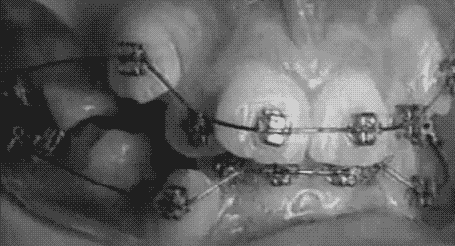

천천히 보고 계시면 움직이는 사진입니다.

클라피씨 브라켓을 자세히 보면

뚜껑처럼 문이 열리면서

교정 아치 와이어를 결찰(고정) 합니다.

클리피씨 브라켓 단면을 보면

교정 철사가

좌우로 잘 통과 할 수 있도록 되어 있어

다른 교정 브라켓 보다 마찰력이

낮다는 점이 중요합니다.